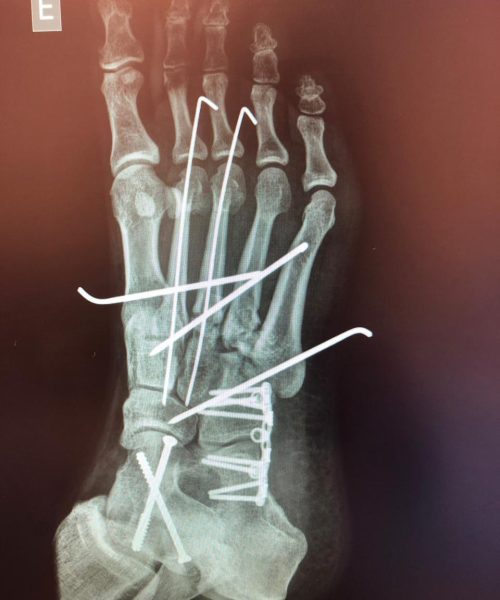

Fraturas no pé e tornozelo referem-se à quebra dos ossos nessas regiões, podendo ocorrer devido a traumas, quedas ou impactos.

Os tratamentos são indicados para pacientes com fraturas que podem variar de simples a complexas, comprometendo a função e a estabilidade.

O tratamento pode incluir imobilização com gesso, tala ou até mesmo cirurgia, dependendo da gravidade da fratura. A cirurgia pode envolver o uso de pinos, placas ou parafusos para fixar os ossos.

Riscos cirúrgicos incluem infecção, má cicatrização óssea e a necessidade de remoção posterior de hardware. O cirurgião deve discutir esses riscos detalhadamente com o paciente.

A recuperação pode variar significativamente, dependendo da gravidade da fratura e do tipo de tratamento. Geralmente, envolve um período de imobilização seguido por fisioterapia para restaurar a função e a mobilidade.